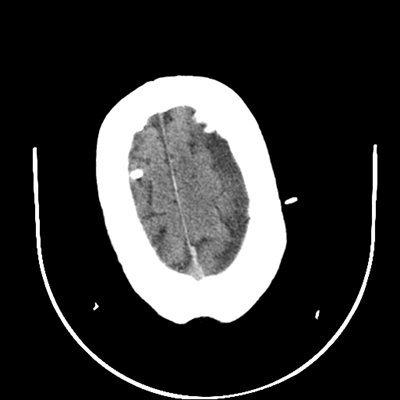

Starting with the non-contrast head CT, we can appreciate that there's actually not much residual subarachnoid blood at all; it's essentially all resorbed already (and cleared through the EVD). The ventricular caliber is stable. With the CTA head (for convenience's sake, the MIPs were shown), it's subtle, but we can see that the PCAs on each side are not as smooth and regular. The right MCA, starting at the bifurcation, also becomes narrower. This is [radiographic] vasospasm. Now, looking at the CT perfusion-- specifically, the Tmax (MTT) map that were selected-- there's clearly some abnormality within the bilateral cerebellar hemispheres and occipital lobes. Not a lot, but it's there. Delving further into this map, we can appreciate that the areas of abnormality are mainly green, signifying that these areas have Tmax > 6 seconds. This is the threshold that is specific, not sensitive, for vasospasm.

Putting this all together, we have thus identified radiographic vasospasm with the vessel imaging, with perfusion abnormalities that are concordant with it. Does the area of vasospasm and hypoperfusion correlate with the patient's clinical exam?

Yes! It does. The patient had a decline in level of consciousness with diffuse loss of motor function. This does correlate to the basilar territory. (Alternatively, bilateral MCA vasospasm could also be responsible, reminding us that a decline in consciousness could technically be focal/multifocal.) Thus, we can say that this patient does have clinical vasospasm. Whether this will develop into irreversible DCI remains to be seen; at least, the non-contrast head CT and the other portions of the CT perfusion (not shown) currently don't [yet] suggest infarction.